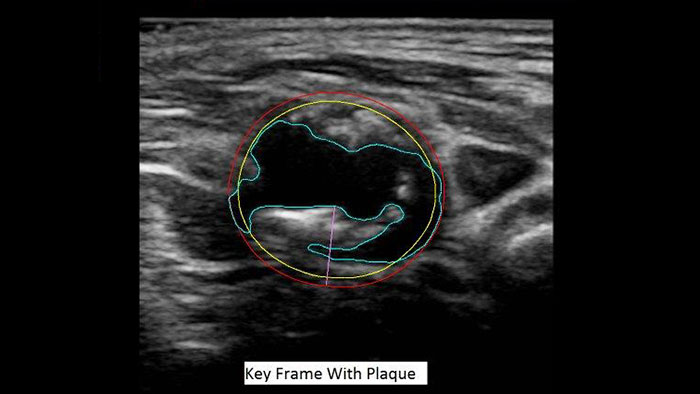

Nowatorska metoda pomiaru objętości płytki miażdżycowej

US Q-App Vascular Plaque Quantification (VPQ) to narzędzie wspomagające użytkownika podczas wszechstronnej analizy objętościowej blaszki miażdżycowej będącej istotnym wskaźnikiem choroby sercowo-naczyniowej. Korzystając z technologii 3D, użytkownik może dokonać automatycznej analizy składu blaszki w oparciu o pozyskaną objętość, określić procent zwężenia naczynia i zmierzyć inne parametry. Wyniki analizy można dołączyć do badań pacjenta.

Korzyści